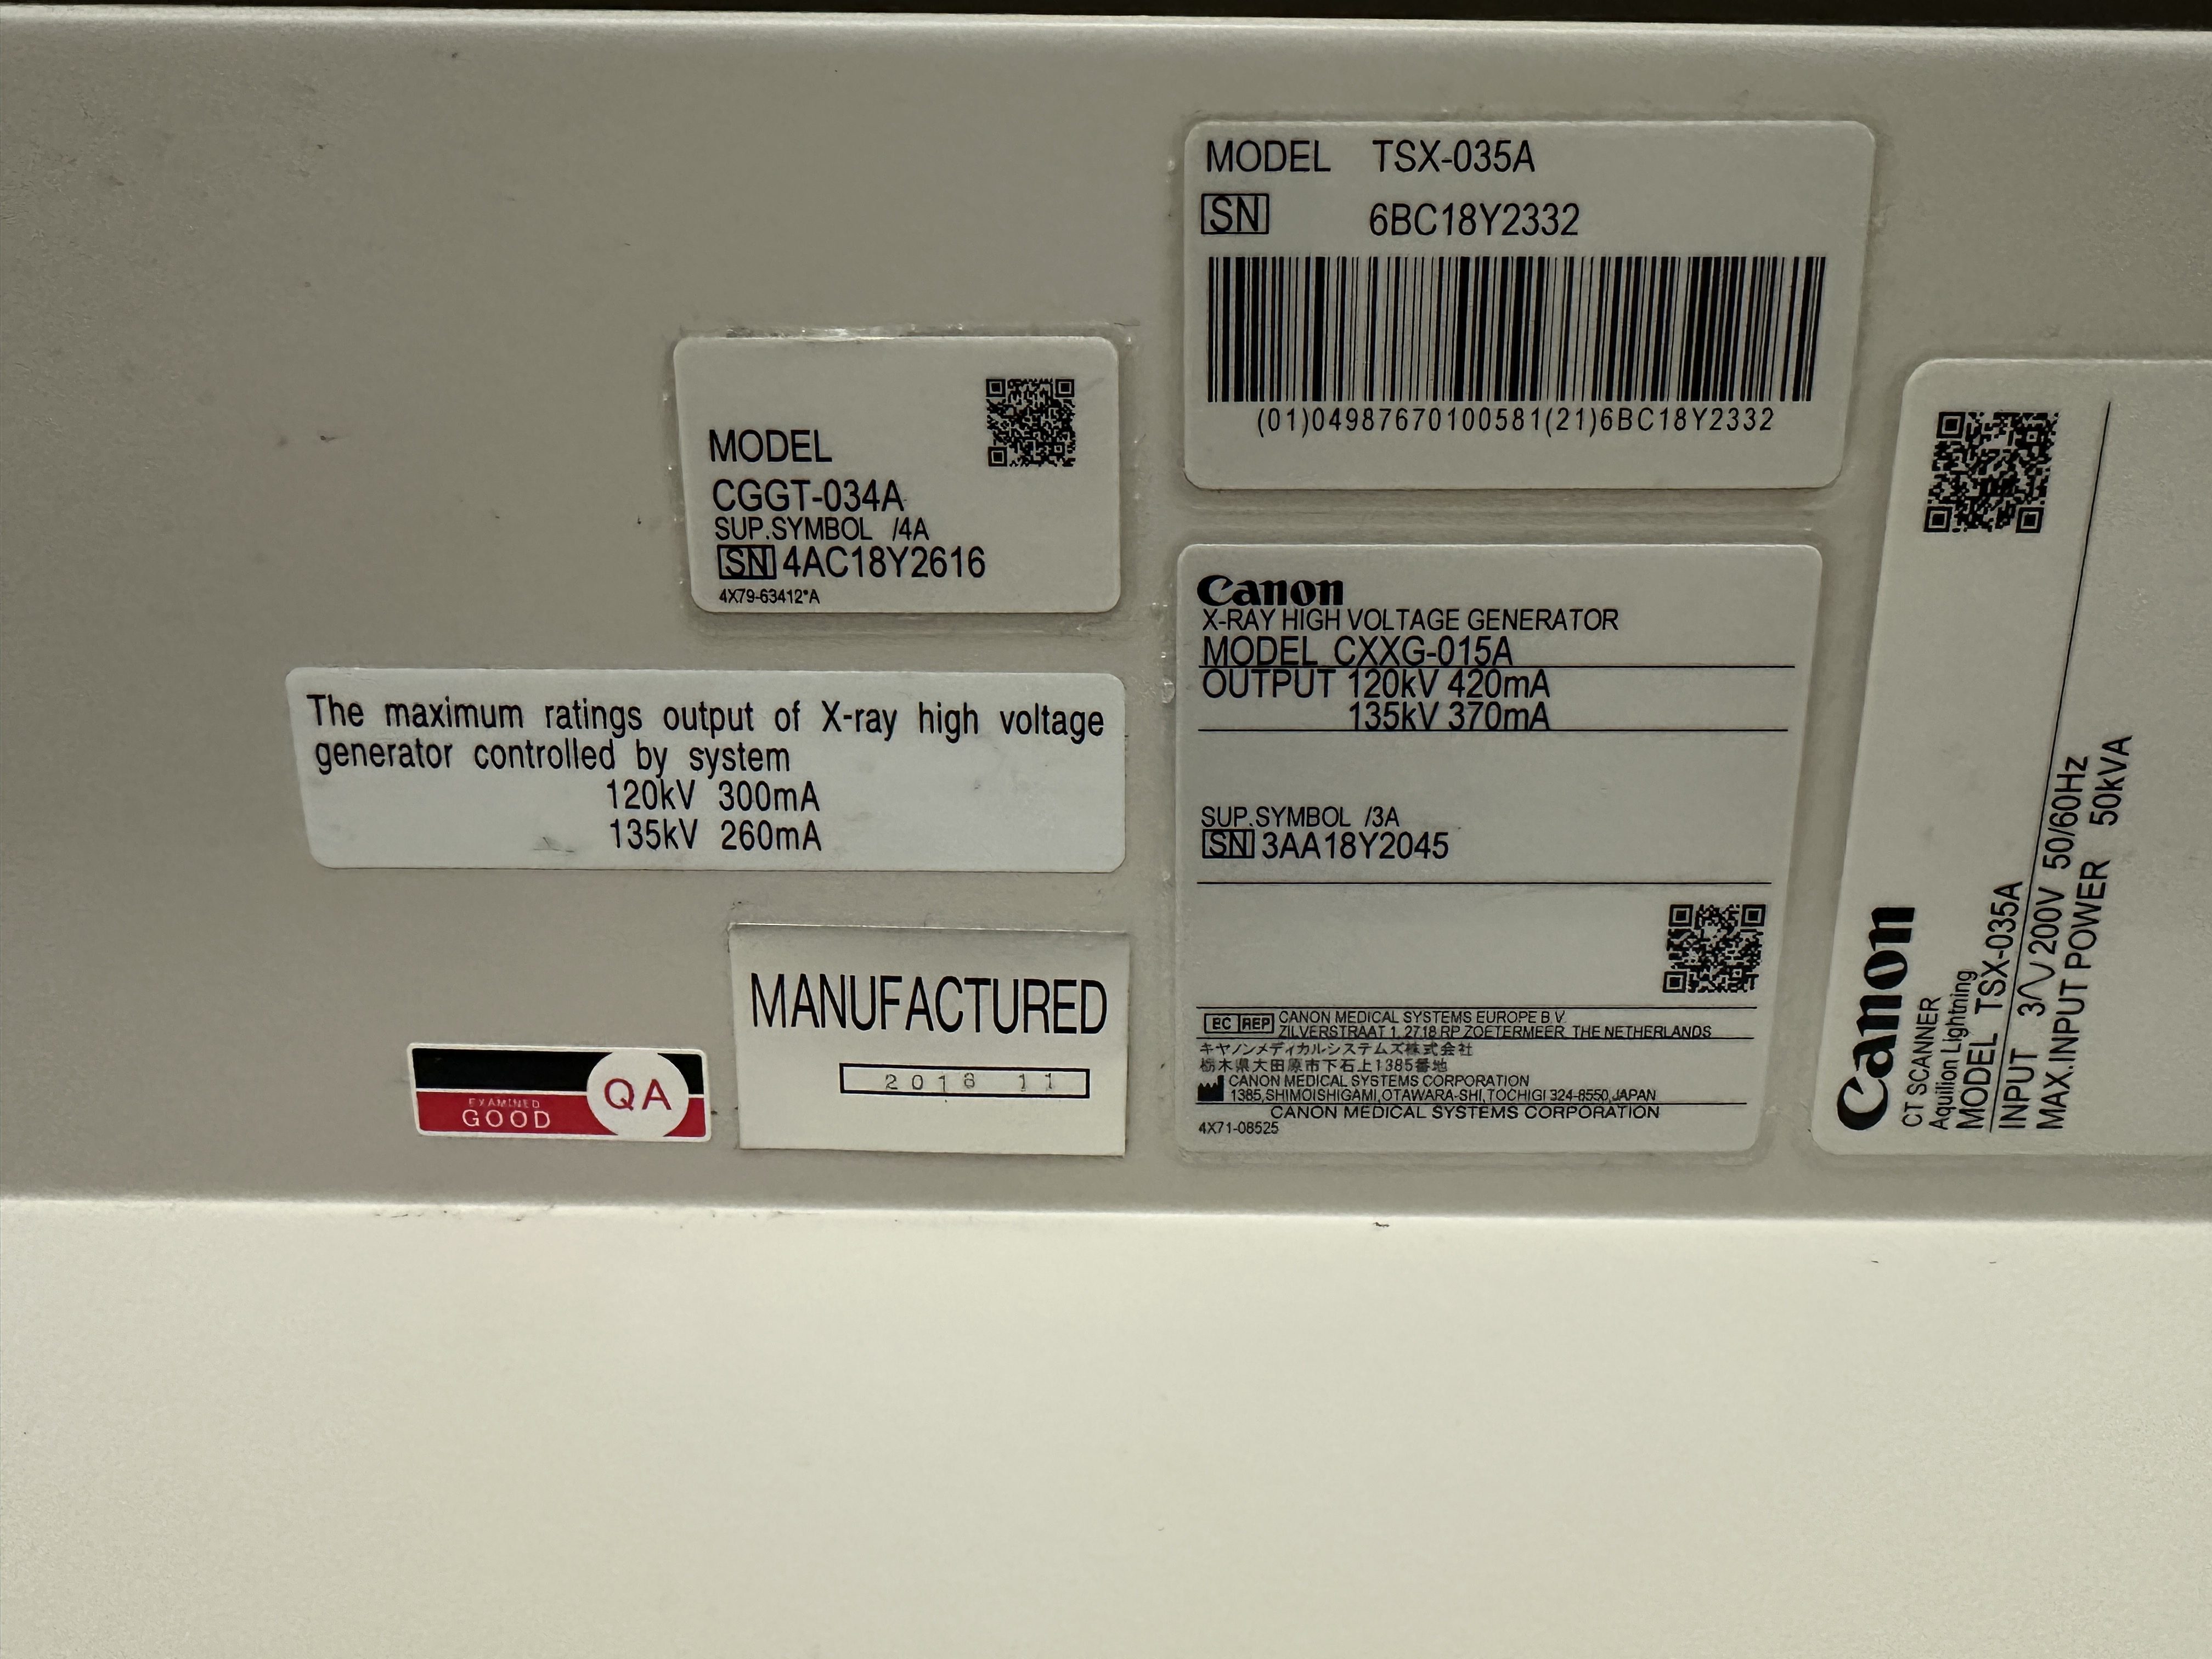

| Manufactured | : | November 2018 |

| Location | : | Japan (NEX325) |